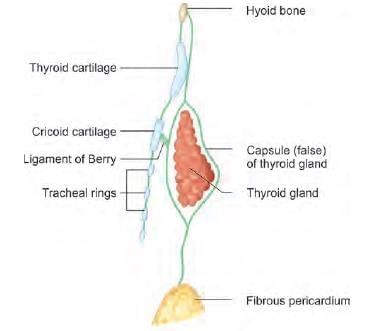

The upward extension of thyroid swelling is prevented by which of the following structure attached to thyroid cartilage? (NEET-PG 2020)